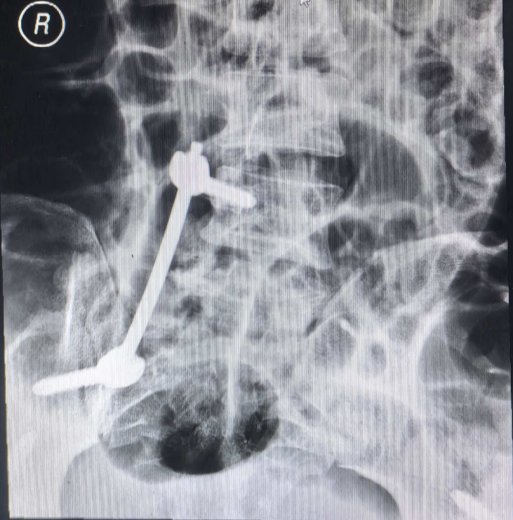

(术后复查X光)

与传统开放手术相比,此项手术是经皮置入腰髂螺钉-棒系统,有力恢复骨盆垂直与旋转稳定性;双侧髂前下棘通道螺钉+皮下预弯钛棒(INFIX)形成张力带,闭合复位固定耻骨支或耻骨联合分离;术中切口小,出血少,手术时间短,术后恢复快,瘢痕小,并发症发生率低。

做好一切术前准备工作后,9月21日,创伤骨科副主任医师沈黎明、主治医师李祯为患者实施了手术。经过一个多小时,顺利完成骨折的复位及骨折的有效固定,术中出血不超过100ml。复查CT显示,骨折部位复位良好,患者体表仅有数个2厘米左右的切口。